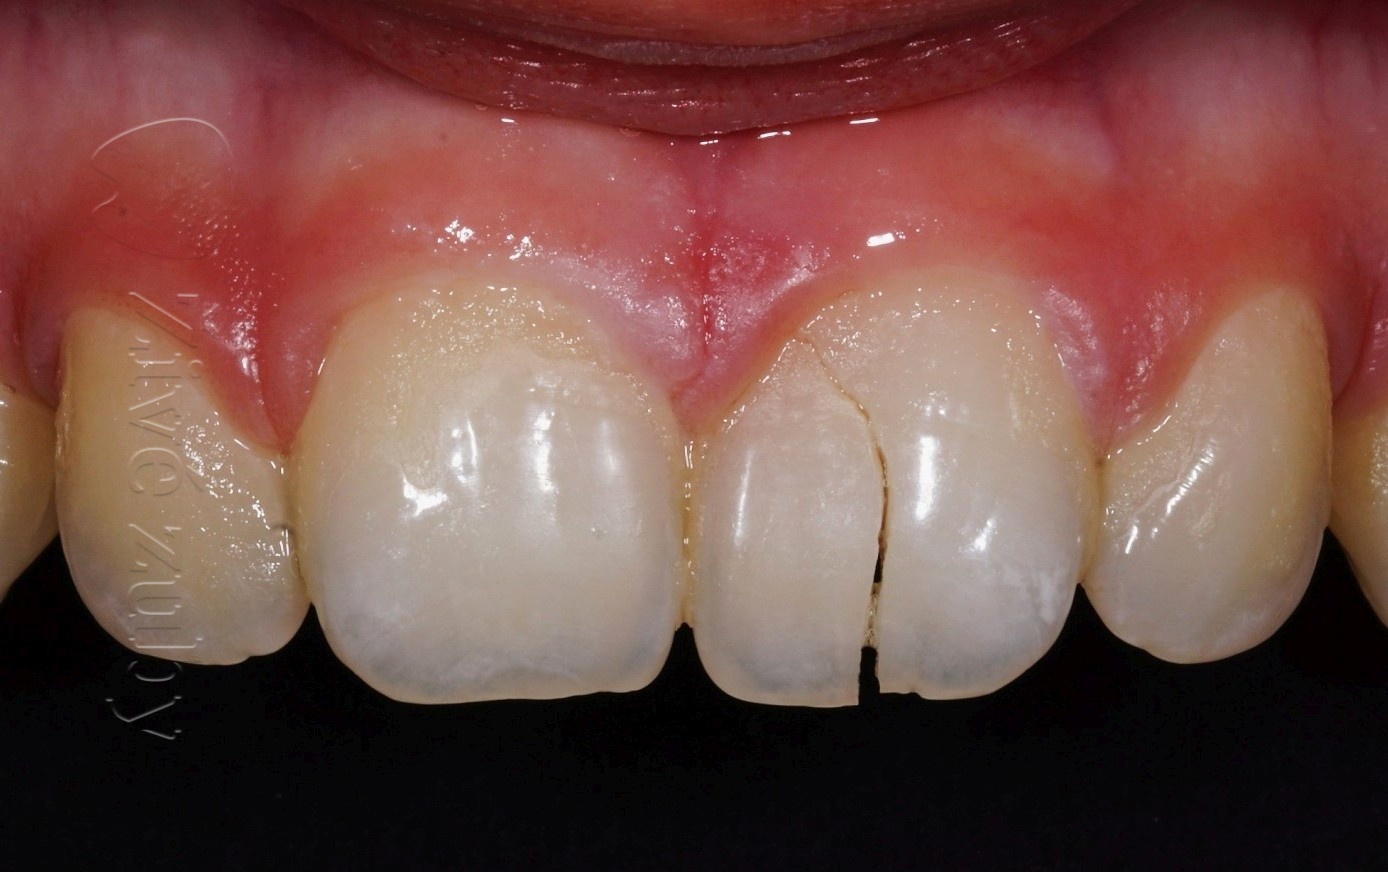

Fraktury zubů

(nekomplikované, komplikované, pulpotomie, … )

Výchozí stav  ——-  Kontrola po 2 letech